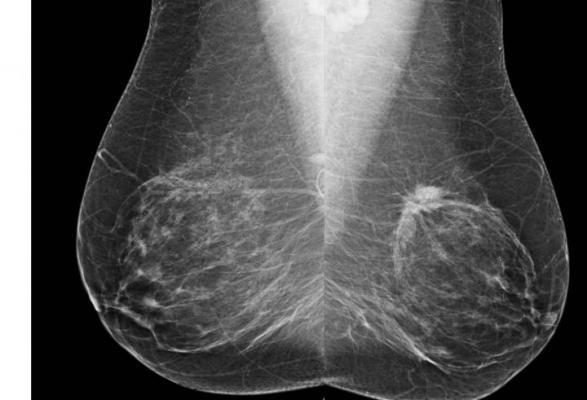

In a study published August 17 in the Journal of Clinical Oncology, researchers updated their current breast cancer risk model, which includes density categories – an important factor in determining the possibility of developing the disease – to one that also includes benign biopsy results.

The first version of the Breast Cancer Surveillance Consortium risk model does not account for non-malignant proliferative conditions diagnosed via biopsy. These include atypical ductal hyperplasia, which raises risk 3.5 to 5 times higher than those without the condition, and lobular carcinoma in situ, which raises risk to 7 to 11 times higher, according to the American Cancer Society.

The researchers, led by Jeffrey Tice, M.D., of UC San Francisco, analyzed data from 1.1 million racially diverse women, aged 35 to 74, undergoing mammography with no history of breast cancer. During follow-up averaging 6.9 years, close to 18,000 women were diagnosed with invasive breast cancer, defined as malignancy that had spread outside the lobules, or milk ducts, and had invaded healthy tissue.